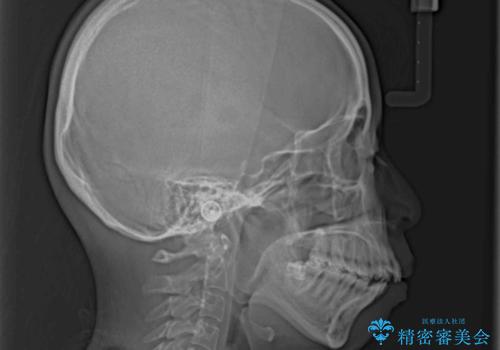

Eラインを改善したい ハーフリンガルによる抜歯矯正

- 口元の突出感を気にして来院された患者様です。

上下左右の第一小臼歯4本を抜歯して口元を下げる治療計画としました。

舌の突出癖が強く、口元を引っ込める力に拮抗してしまい、抜歯スペースを閉じるまでに時間がかかりました。